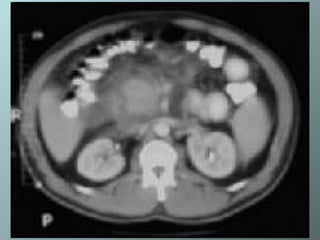

Necrosis pancreática: no se advierte intensificación del cuerpo del pancreas. Hay fluido peripancreático delante de la cabeza del páncreas

Necrosis pancreática

Necrosis pancreática: nose advierte intensificación del cuerpo del pancreas. Hay fluido peripancreático delante de la cabeza del páncreas